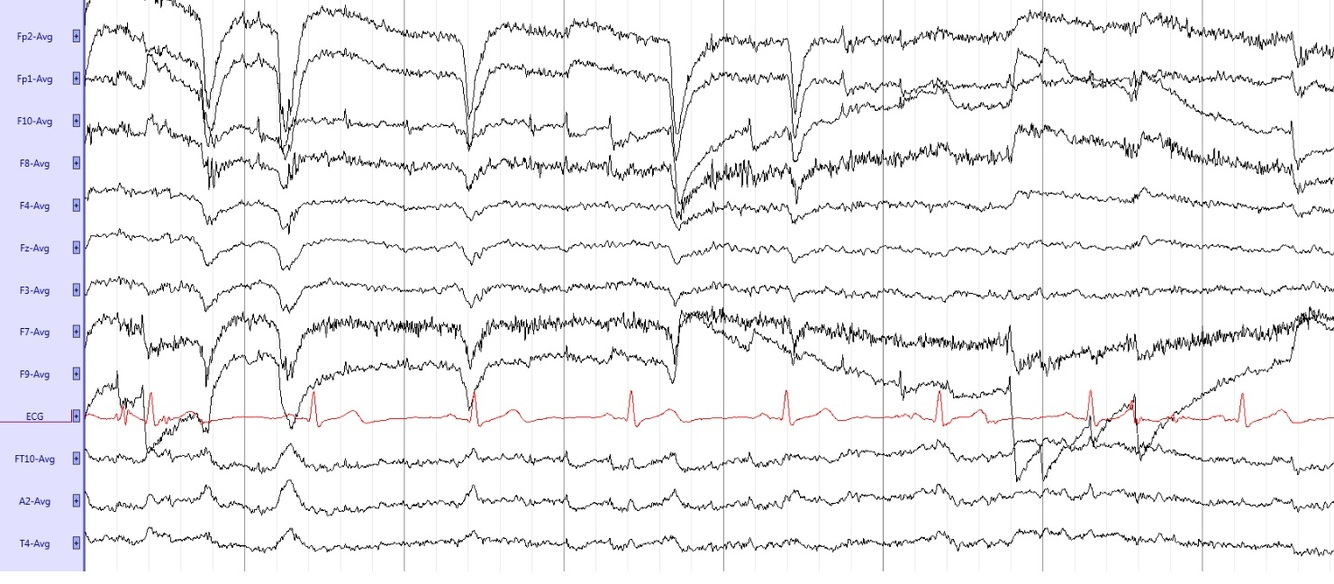

Describe the Blink artifact. what is the underlying phenomenon?

Large positive (downward) deflection as the eye move upward in its orbit. Only seen in the frontal leads (F3 or F7).

Is a key component of normal, awake EEG.

It is caused by the Bell’s Phenomenon. The eyes’ cornea is positively charged and retina is negatively charged; when you blink, the eyes roll up slightly, and the cornea moves closer to the frontal electrodes Fp1 and Fp2, which thus see a positive signal that is reflected on EEG.

Describe ECG artifacts

Look like negative spikes time-locked to the QRS complex